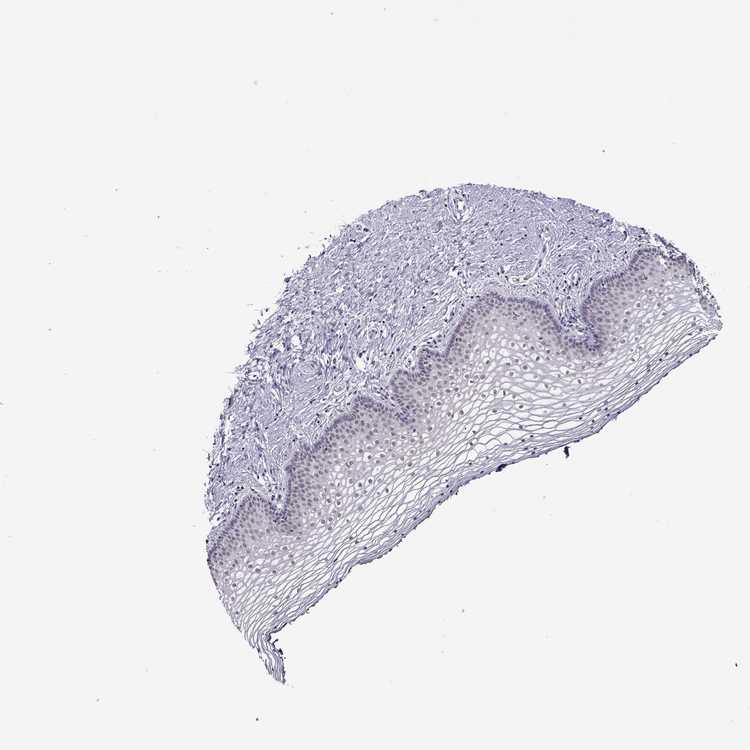

TISSUE PRIMARY DATA VAGINA Show tissue menu

Vagina

VAGINA - Antibody stainingi

Antibody staining in the annotated cell types in the current human tissue is reported as not detected, low, medium, or high, based on conventional immunohistochemistry profiling in selected tissues. This score is based on the combination of the staining intensity and fraction of stained cells.

Each image is clickable and will lead to virtual microscopy that enables deeper exploration of all samples and also displays staining intensity scores, fraction scores and subcellular localization as well as patient and tissue information for each sample.

Antibody HPA005516Antibody CAB015427

Squamous epithelial cells LowNot detected